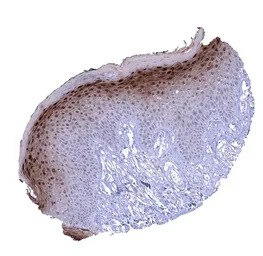

IHC-P analysis of human skin tissue section using GTX04453 Cystatin A antibody [MSVA-461M] HistoMAX.

In the skin a nuclear and cytoplasmic Cystatin A immunostaining is predominantly seen in the granular cell layer. The staining intensity decreases towards the basal cell layer.